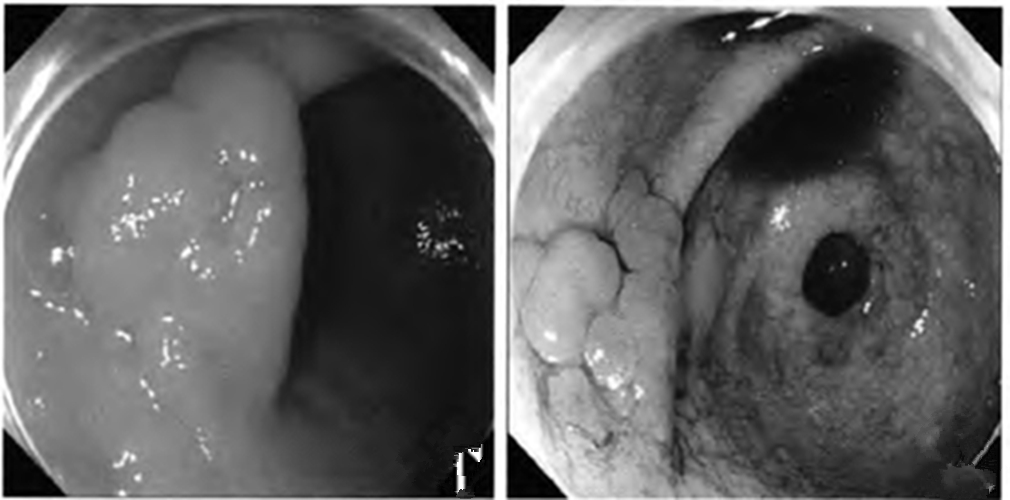

慢性胃炎圖片

慢性胃炎